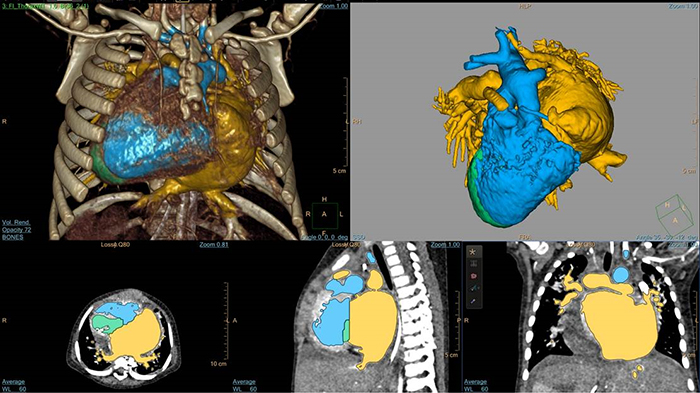

Análise D-TGA de 5 dias com HeartNavigator

3D Modeling com IntelliSpace Portal